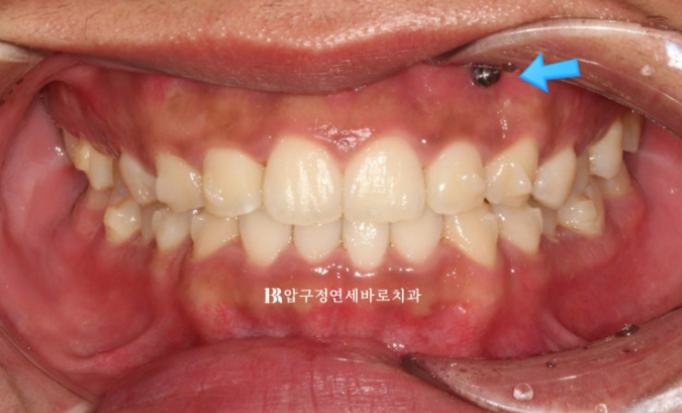

The bite after wearing all 14 aligners for 4 months.

The patient diligently wore the elastics in the blue-arrow area, and over 4 months the tilted occlusal plane and deep bite were successfully corrected.

24.07

When smiling, one side no longer appears to come down lower.

The result was good and the patient was satisfied, so treatment was completed without remaking the aligners.